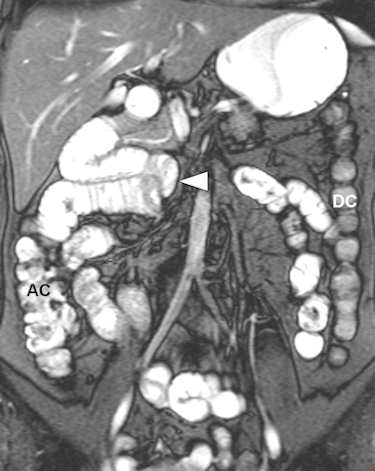

Among the bowel and mesenteric diseases to be aware of are internal hernia, intussusception, neuroendocrine tumor, and familial Mediterranean fever, all of which can mislead radiologists to erroneously diagnose active Crohn's disease, Kavaliauskiene stated. Often, knowledge of findings in these diseases can be sparse.